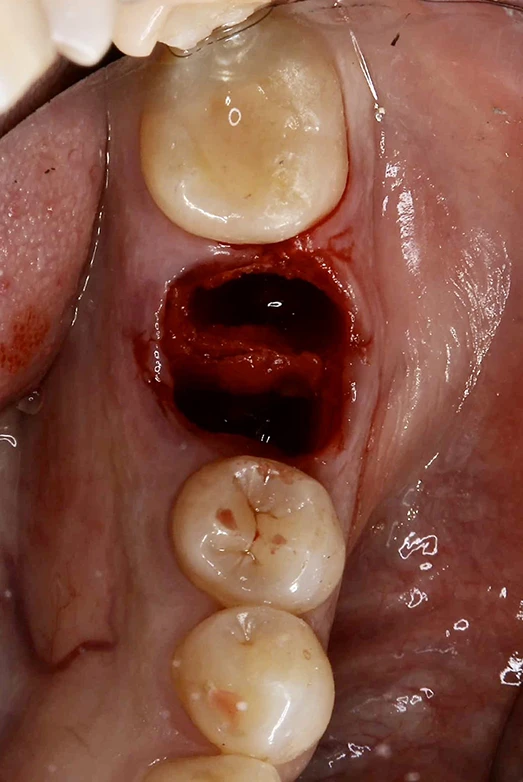

40代、女性、左下噛むと痛いこと主訴に来院され、インプラント治療を行いました。

| 診断結果 | 左下6番歯根破折 |

| 治療内容 | 抜歯即時インプラント |